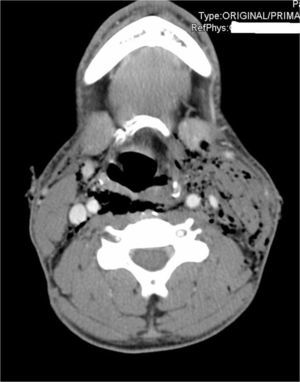

Imagen transversal del angio-TC cervical. Enfisema subcutáneo, sobre todo a nivel izquierdo que diseca hasta mediastino, con posible lesión puntiforme del seno piriforme izquierdo, no se objetivan lesiones de vasos cervicales, ni extravasación de contraste oral, ni hematomas, ni otras alteraciones.

Paciente de 28 años, sin antecedentes de interés, remitido a nuestro centro por intento autolítico con objeto punzante (cuchillo) a nivel cervical. Se objetiva disfonía, sin disnea. A la exploración: constantes normales, saturación de oxígeno 100% y escala de coma de Glasgow de 14 puntos. Presenta 5 lesiones a nivel de la zona II cervical (3 heridas incisas superficiales en lateral derecho y 2 heridas inciso-contusas que sobrepasan platisma en lado izquierdo) con crepitación a la palpación en el lado izquierdo. Anisocoria con miosis del ojo izquierdo y ptosis ipsilateral (fig. 1), resto de exploración normal. Radiografía cervical y tórax con enfisema subcutáneo sin neumotórax. Angio-TC con contraste oral (fig. 2). Laringoscopia: parálisis de la cuerda vocal izquierda en posición paramediana, junto con una parálisis del hipogloso izquierdo, no se puede descartar lesión puntiforme en seno piriforme izquierdo. Se realizó un tratamiento conservador con antibioterapia intravenosa, dieta absoluta y control radiológico con nuevo TC cervical en 24h que objetivó una mejoría con disminución del enfisema subcutáneo y neumomediastino. Tras iniciar progresivamente tolerancia, el paciente evolucionó favorablemente con controles analíticos y radiológicos dentro de la normalidad. Fue dado de alta al 7.° día del ingreso, previo control por psiquiatría. En el seguimiento en consultas externas al año, el paciente mantiene el síndrome de Horner, pero ya no presenta parálisis de la cuerda vocal ni del hipogloso izquierdo.

Así, ante la presencia de un traumatismo penetrante cervical que curse con un síndrome de Horner, hay que sospechar una lesión vascular asociada, como es la disección de la arteria carótida6, de ahí que la prueba diagnóstica de elección sea el angio-TC7. Sin embargo, en nuestro caso es llamativa la ausencia de dicha lesión a pesar de su íntima relación, asociando solo una pequeña lesión puntiforme en el seno piriforme izquierdo que originó un importante enfisema y neumomediastino, que se trató conservadoramente con éxito. Además, la presencia del síndrome de Horner, disfonía y enfisema subcutáneo son signos blandos en las lesiones penetrantes cervicales, que permiten un estudio diagnóstico completo.